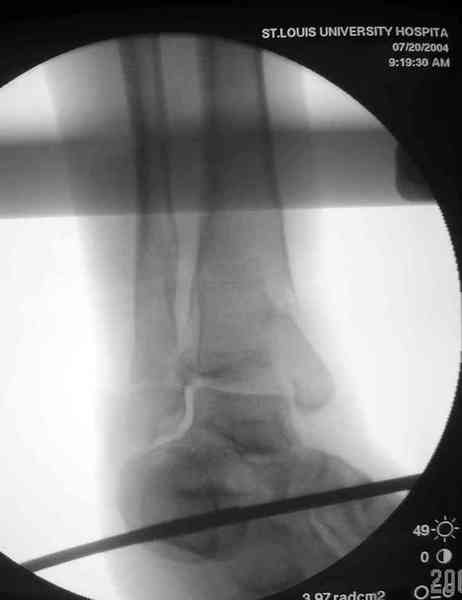

Яков изложил все необходимые аспекты лечения переломов пилона, и, не желая менять тему, решил выставить нашу точку зрения в двух клинических примерах.

При лечении внутрисуставных переломов типа "Pilon"

или "Tibial Plateau" на голени, применение простых

наружных фиксаторов типа "Spanning ExFix" или "Travelling ExFix" стал одним из стандартом этапного лечения.

В первые часы после поступления больным экстренно накладывается простой фиксатор из двух поперечно проведенных стержней или сооружается "Delta

Frame" в зависимости от места локализации, и проводится дистракция.

Здесь выставлена пара случаев перелома пилона, оба

случая леченные этапным наружным фиксатором.